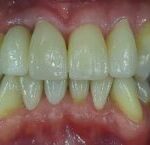

Vorher: Alte Implantat-Krone kleinerer Schneidezahn ; nicht ansprechende Ästhetik Frontzähne

Nachher